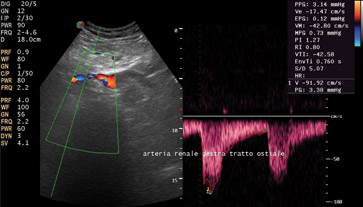

Con l’ecocolordoppler a tutto ciò viene aggiunta la visualizzazione del flusso ematico all’interno dei principali vasi sanguigni. Tale visualizzazione viene assunta attraverso il collegamento in tempo reale di una immagine ecografica bidimensionale con un segnale doppler pulsato. L’ecocolordoppler è indicato per ilmonitoraggio e la diagnostica delle stenosi arteriose e venose, degli aneurismi, delle trombosi e delle insufficienze venose.